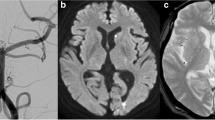

Imaging characteristics of chronic hemosiderin depositions

A tram-track sign was observed in 34 of 50 (68 %) cases with subpial HD (Fig. 3). Imaging characteristics of chronic HD are detailed in Table 2. It was noted that the linear subpial HD in our cases resembled the linear superficial cortical hemosiderosis which has been reported in patients with cerebral amyloid angiopathy [15].

T2*-weighted gradient-echo MRI in a 49-year-old patient obtained 4 years after aneurysmal SAH. Chronic hemosiderin depositions are observed as superficial linear hypointensities in multiple cortical sulci (white arrows). There is also a focal parenchymal hemosiderin deposit (black arrow) after surgical treatment (ventricular catheter)

Recently, it has been reported that subarachnoid hemosiderosis and superficial cortical hemosiderosis are signs of cerebral amyloid angiopathy [15, 20]. It is assumed that repeated minor subarachnoid bleeds from small arterial and venous vessels affected by amyloid angiopathies lead to chronic HD and that hemosiderin on subarachnoid membranes can be taken up into subpial cortical layers. On T2*-weighted images, superficial cortical hemosiderosis is typically characterized by thin hypointense lines on both cortical surfaces adjacent to a cortical sulcus which shows hyperintense signal (“tram-track sign”). This sign has been reported to be highly specific for amyloid angiopathy [15]. It is a significant finding of our study that in most cases, the typical imaging characteristics of superficial cortical hemosiderosis can also be observed in the chronic phase after single aneurysmal SAH. In our series, we observed single linear superficial HD in 50 of 90 cases (55.5 %) and the tram-track sign in 34 of 90 cases (37.8 %). To the best of our knowledge, this has not been reported before.